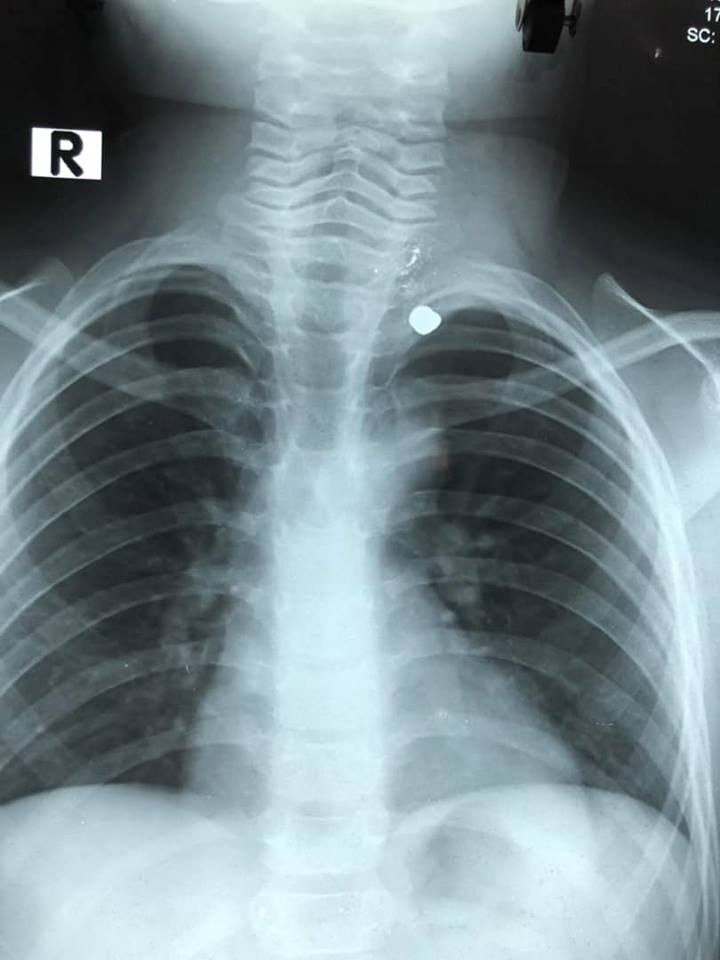

Hình chụp X Quang cho thấy vị trí của viên đạn. Ảnh: Dân Việt

Tại Khoa Cấp cứu, bé được thăm khám, chụp X Quang ngực. May mắn, đạn đi từ cổ đến đỉnh phổi trái nhưng không xuyên vào mạch máu lớn, khí quản hay tim. Sau đó, bé được đưa vào Khoa Ngoại tổng hợp.

Tại khoa Ngoại tổng hợp, sau khi thăm khám, hội chẩn khoa, các bác sĩ nhận định nếu mổ mở đi từ vùng cổ có thể rất khó vì mạch máu, thần kinh vùng này nhiều và vết mổ sẽ rất xấu. Vì vậy, ekip phẫu thuật quyết định phẫu thuật nội soi lồng ngực để lấy viên đạn.

Theo ghi nhận lúc phẫu thuật, viên đạn nằm ở đỉnh phổi trái, cạnh động mạch dưới đòn trái. May mắn, mạch máu lớn và thần kinh không bị tổn thương. Sau phẫu thuật, sức khỏe bé ổn định và đã được xuất viện, theo báo Dân Việt.